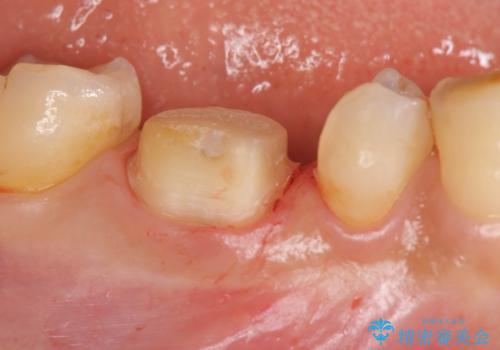

治療途中の歯 セラミック治療を希望され来院

- 治療途中で数ヶ月放置してしまった歯のセラミック治療を希望され来院されました。

セラミッククラウン・セラミックインレーを用いた精密治療を計画します。

- 20.9万円(ジルコニアクラウン・仮歯 ・セラミックインレー)費用は治療当時の料金となります

審美性、化学的安定性に優れるセラミック治療を行うことができました。